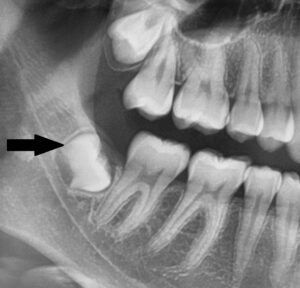

Hier sieht man das Problem:

Weisheitszähne können Infektionen verursachen – Die erste Abbildung zeigt einen Weisheitszahn (schwarzer Pfeil), der aufgrund von Platzmangel nicht vollständig in die Mundhöhle ragt. Auf der zweiten Abbildung sieht man diesen Weisheitszahn (schwarzer Pfeil), der teilweise noch mit Schleimhaut bedeckt ist. Die dadurch entstehende „Zahnfleischtasche“ bildet ein Reservoir für Bakterien und kann Entzündungen begünstigen. Es empfiehlt sich deshalb, solche Zähne zu entfernen.